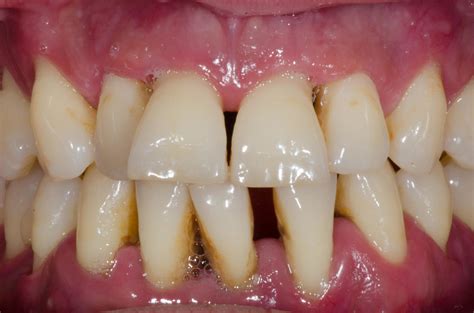

• Receding gums: Gums pull away from teeth, making teeth appear longer

In advanced gingivitis, the visual changes are unmistakable. The gums appear bright red or purple, significantly swollen, and may feel spongy to the touch. Bleeding occurs easily and frequently, sometimes even spontaneously. The gum tissue may begin to recede noticeably, exposing more of the tooth surface and potentially the root. At this stage, without intervention, gingivitis is on the verge of progressing to periodontitis, which involves bone loss and is irreversible.

It's important to distinguish gingivitis from other oral health conditions that may have similar appearances. Periodontitis, the advanced form of gum disease, looks similar to severe gingivitis but includes additional signs like deep pockets between teeth and gums, loose teeth, and visible bone loss on X-rays. Unlike gingivitis, periodontitis causes permanent damage.